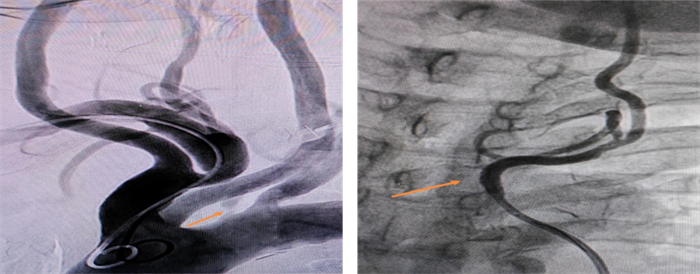

手術(shù)前(左):左側(cè)椎動(dòng)脈開口重度狹窄

手術(shù)后(右):左側(cè)椎動(dòng)脈開口支架植入后狹窄解除

整個(gè)術(shù)程迅速且順利,術(shù)后造影證實(shí)支架位置良好,打開完全,狹窄解除,血流通暢。術(shù)后第二日患者訴頭暈明顯改善,未訴特殊不適,正常下床活動(dòng)。患者及家屬向心血管內(nèi)科醫(yī)護(hù)團(tuán)隊(duì)由衷地表示感謝。